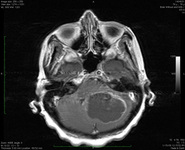

Infarto cerebelar bilateral agudo, observado na ressonância nuclear magnética de sequência de imagem ponderada por difusão

Do acervo de Dr. S. H. Subramony; usado com permissão